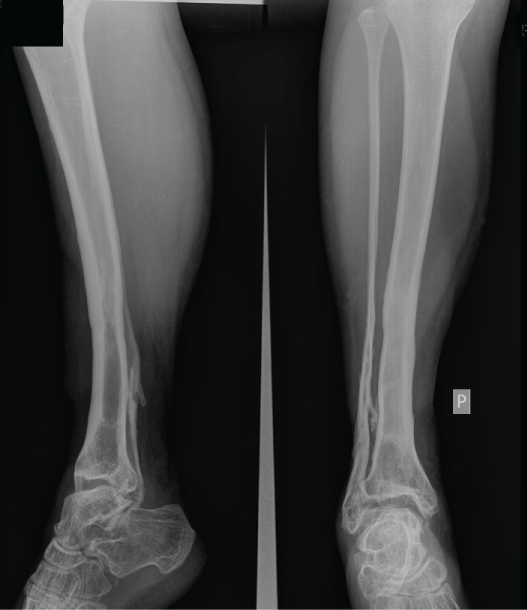

A 10-year old girl had been admitted to our Department after having been run over by a tram. She had a crush injury of the left foot (8 MESS score) and a Gustillo-Anderson IIIB open tibial fracture on the right side (6 MESS score) (Figure 1). The plantar sensation and pulse on the right foot were present. Despite multiple debridements, local and parenteral antibiotics and vacuum therapy of the left foot, the deep infection with osteomyelitis ensued that required the amputation of left foot on the level of ankle joint (Figure 2).

Figure 1: Crush injury of the left foot and an Gustillo-Anderson IIIB open tibial fracture on the right side